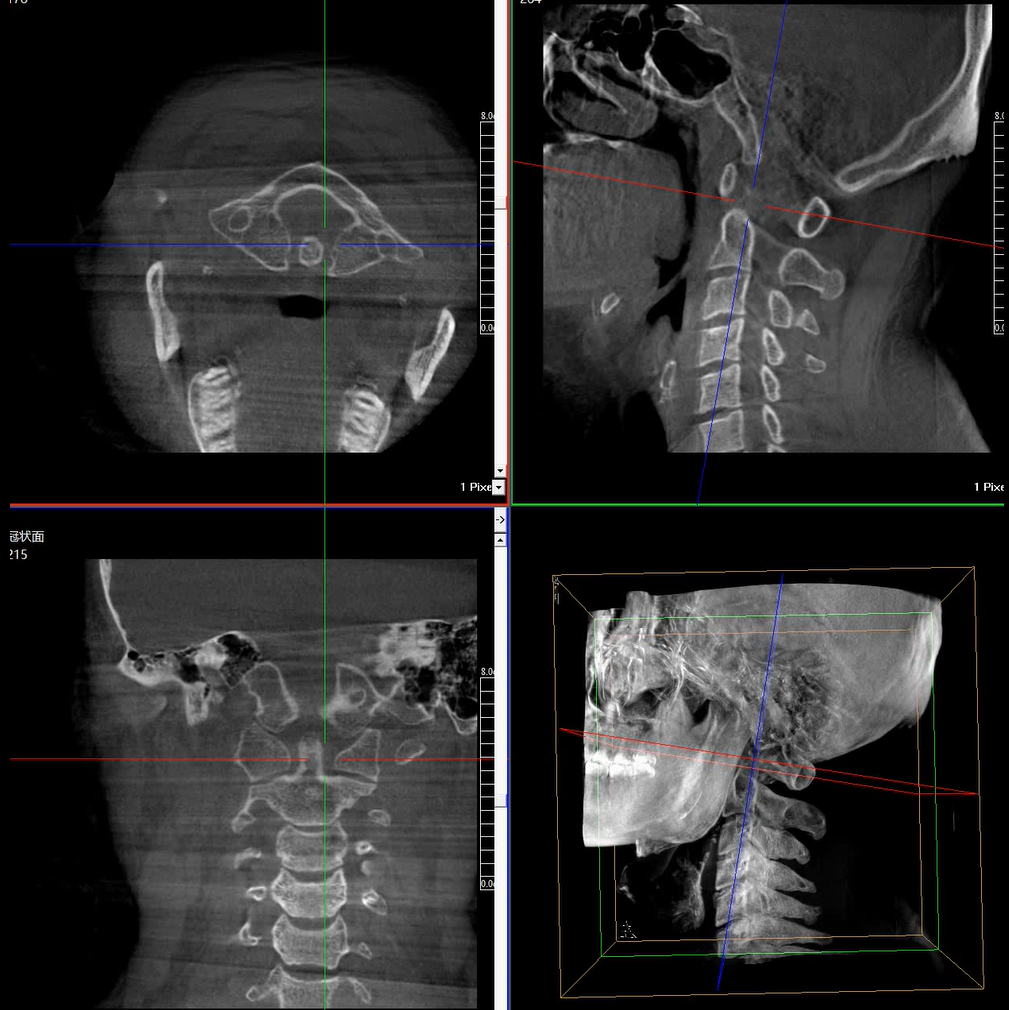

提供更大的術(shù)中三維成像視野,采集更多圖像信息,可一次拍全全段頸椎、全段腰椎、七節(jié)胸椎、雙側(cè)骶髂關(guān)節(jié)、股骨頭及單側(cè)盆骨。